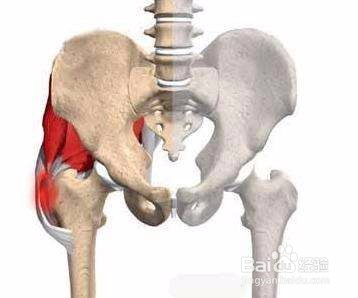

3、误区三,股骨头坏死只能进行置换。

股骨头坏死的治疗防止有许多种,进行股骨头置换有很大的手术风险及后续问题,要慎重考虑。除了股骨头置换还有一些其他的治疗方式,比如中医的饱受治疗可根据患者自身需要进行选择。